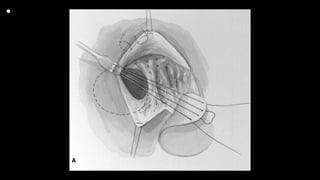

• Figures 1 and 2 Standard cardiopulmonary bypass with direct

bicaval cannulation is achieved, even in the neonate, at

a systemic temperature of 28°C to 32°C (cannulas removed for

clarity). A vent is placed through the right superior

pulmonary vein and cold blood cardioplegia administered after

aortic cross clamping. A right atriotomy is made parallel

and close to the right atrioventricular groove. Placing the incision

in this location assists in the exposure by elevating the

anterior wall of the right ventricle and tricuspid valve with the

stay sutures inserted along the atriotomy. The ventricular

septal defect is visible behind the anterior leaflet of the tricuspid

valve. Traction sutures are placed in the anterior and

septal leaflets of the tricuspid valve. In the neonate, a patent

foramen ovale is generally left open, but is closed in older

infants